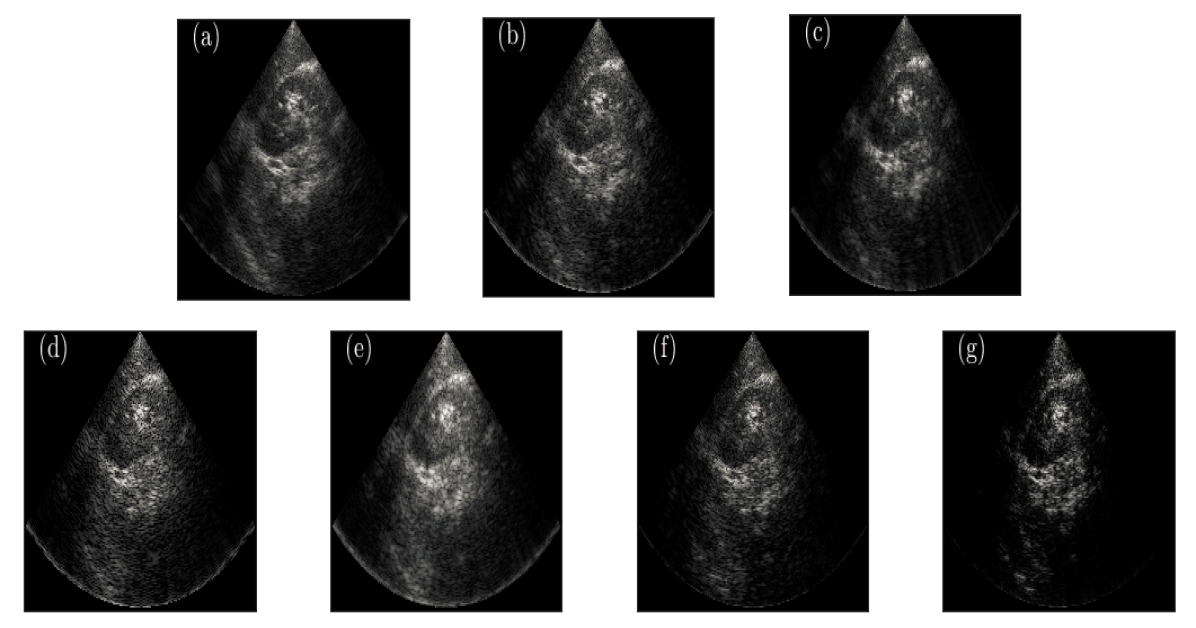

In Table II, quantitative evaluation of CNR for a tissue-mimicking phantom scan is evaluated. As can be seen, in all cases our method outperforms NESTA. In addition, the second dataset reconstructed using NESTA leads to the lowest CNR, which indicates that contrast between noise the signal of interest almost does not exist. These results indicate that our method is much more robust to a reduction both in sampling rate and in the number of acquiring channels than NESTA reconstruction. The resulting images from the phantom scans are presented in Fig. 4. For visually better examining the results, zoomed-in images are given in Fig. 5. While in (a)-(c) all three options depict approximately the same visual quality. Comparing (d) and (e) should be done more carefully, one may claim that (e) exhibits worse resolution with regards to (d), however, there are two major disadvantages in the latter. First, due to the relatively high reduction in the number of samples per image line, the recovered image shows high granularity, combined with the second drawback, which is low contrast, as calculated and can be seen, earns it difficult to notice actual reflectors that are easily seen in (e). Lastly, in (f)-(g), both contrast and resolution are visually proved to be much better in (g).

Images produced from in-vivo scan data are presented in Fig. 6. It can be seen that the proposed method, over the first dataset of 230 samples yields results that are visually better than those produced with DAS or NESTA. Moreover, in the case of 130 samples per image line, the proposed method outperforms NESTA. The image reconstructed using NESTA suffers from high granularity that results from the high dilution factor and can be considered as an artifact. In addition, testing the proposed method over the spatially and temporally diluted data presents better image contrast in comparison to NESTA and DAS, a result that agrees with previously calculated CNR.